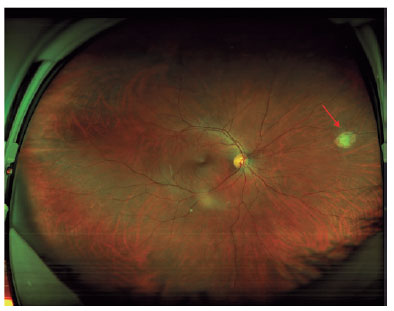

A 32-year-old vegetarian woman developed a severe headache, myalgia, and fever. After 8 days, she was hospitalized in an intensive care unit with symptoms of meningitis. IgG and IgM (ELISA) for toxoplasmosis was positive but she did not receive specific systemic treatment for toxoplasmosis. Three months later, an ophthalmological evaluation confirmed the presence of active retinochoroiditis in the right eye (Figure 3). The final visual acuity was 20/20 in both eyes.

Figure 3. Wide field fundus color photography. The arrow shows a peripheral retinochoroiditis lesion 3 months after the onset of systemic acute toxoplasmosis.